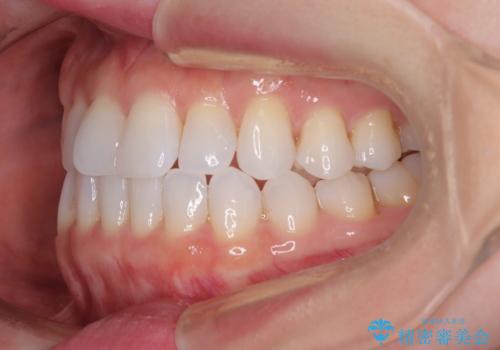

前歯のデコボコをインビザラインで綺麗に

- 上下前歯の叢生を気にして来院された患者様です。

インビザラインでの治療を希望されていて、デコボコの程度が中等度であり、安価なパッケージにて対応可能と判断されたため、インビザライン・モデレートを用いて矯正治療を行うこととしました。